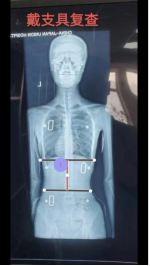

案例3:患者,13岁,青少年特发性脊柱侧弯。考虑其尚处发育期,需兼顾矫正与生活质量的需求,我科室应用3D打印个性化矫形器进行治疗,通过三维扫描获取患者躯干精准数据,经生物力学模拟设计后,3D打印出轻量化、透气且完全贴合的个性化矫形器,不仅实现了显著的即时矫正效果、有效控制了侧弯进展,更凭良好的佩戴舒适度提升了患者依从性。该技术以最小的负担,护航青少年患者的脊柱健康与正常成长,意味着医院逐步形成了脊柱侧弯手术与非手术的完整治疗体系。